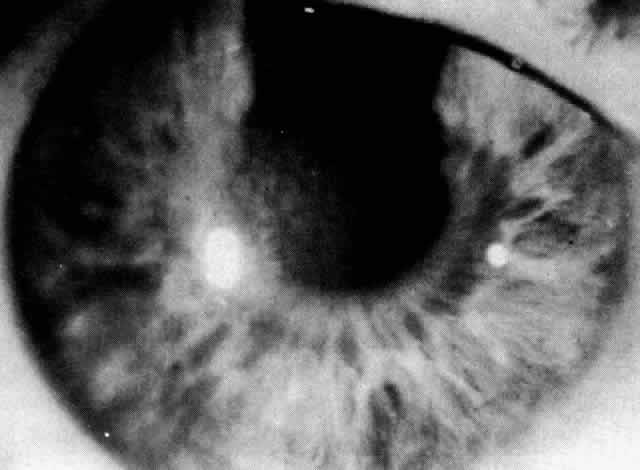

The most common findings are the maplike opacities (Figs. 1 AND 2), which can be detected by wide oblique illumination.8 The dot changes (Fig. 3) are seen by direct illumination, and fingerprint lines (Fig. 4) often need indirect illumination from the iris or retroillumination for detection. The distribution of the lesions can change over time.

Fig. 2. Epithelial basement dystrophy: geographic changes shown in retroillumination.